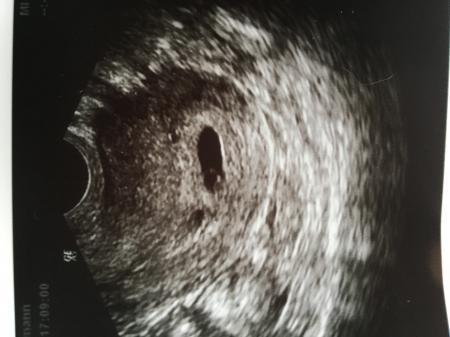

Bin heute 6+0 gewesen und habe am 30.3 Wieder einen Termin Das Herz habe ich noch nicht gesehen aber es ist alles zeitgerecht entwickelt

Bild zu